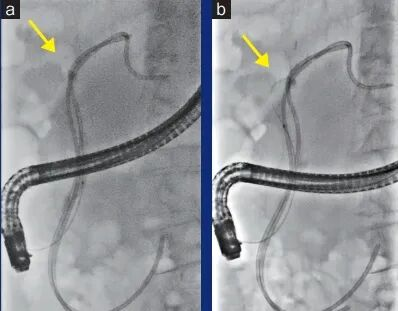

ERCP对影像的依赖程度远高于多数内镜操作。胆管分支细、路径变异多,导丝、网篮等器械尺度细微,稍有伪影或对比度不足,都可能影响操作判断。Ultimax-i X搭载 “Accent”高清引擎,这一技术由佳能医疗与内镜头部企业奥林巴斯(OLYMPUS)联合研发,采用建立在真实病例数据基础上的智能算法,使影像中微小结构更易显现。临床验证显示,对比度可提升 2–2.4 倍,导丝、网篮、支架等ERCP关键器械更易辨识。日本神户大学内镜中心的一例高度胆管狭窄病例(下图)显示,在常规透视模式(a)下导丝难以被识别,而开启Accent模式(b)后,导丝走向在影像中清晰呈现,可视性大幅提升,为后续操作争取了宝贵时间。